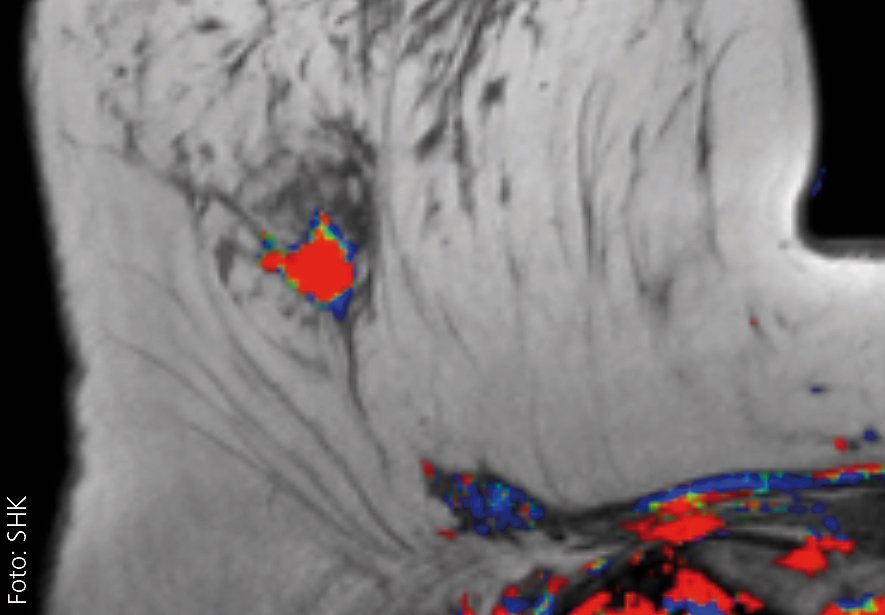

Bildgebung bei Mammakarzinom im Fokus

In den vergangenen Jahren hat sich die Palette möglicher Bildgebungen von Tumoren der Brustdrüse deutlich weiterentwickelt. Dies ist insbesondere technischen Innovationen in der Radiologie zu verdanken. Eine frühe Tumordiagnostik ermöglicht bessere therapeutische Optionen und erhöht häufig die Aussicht auf Heilung...

Der Vortrag stellt die aktuellen Möglichkeiten der Bildgebung der Brustdrüse vor und erläutert die innovativen technischen Weiterentwicklungen der jüngsten Zeit sowie die hier verfügbaren Optionen der histologischen Sicherung. Hinzu kommt ein kurzer Einblick in die sogenannte bildgebende Nachsorge, also die radiologische Diagnostik nach behandeltem Mammakarzinom, die wichtig ist, um ein neuerliches Tumorleiden auszuschließen. Es wird auch auf häufig geäußerte Ängste betroffener Frauen eingegangen werden und wie gewohnt Gelegenheit zum gemeinsamen Gespräch geben.